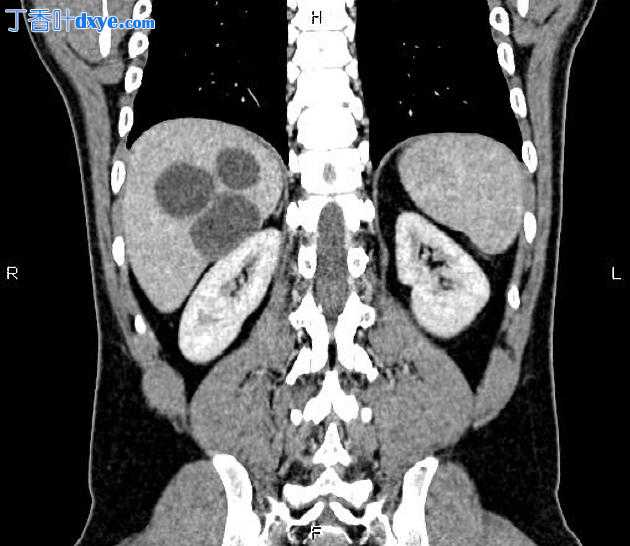

Axial C+ delayed

5.jpeg

在右肝叶小于 55 mm 处可见三个相邻的厚壁囊性病变。

此外,还描绘了一个直径为 15 毫米的低密度肝病灶,位于第 4 肝段(Couinaud 的命名法),显示早期外周、结节状强化和向心性充盈。特征与血管瘤最相容。